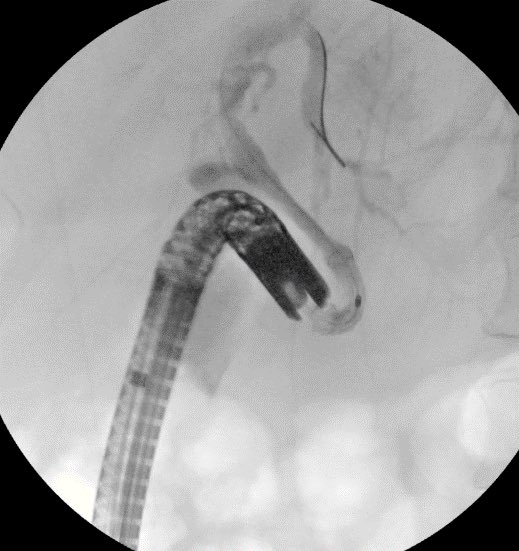

Failed ERCP due to acute angulation of papilla from pancreatic mass. We performed EUS guided RV ERCP as there were minimal dilation of the CBD. 19G Boston Scientific FNA needle followed by .025 wire passage is our preferred approach for biliary access in these cases. #GITwitter

Failed ERCP due to acute angulation of papilla from pancreatic mass. We performed EUS guided RV ERCP as there were minimal dilation of the CBD. 19G <a href="/bostonsci/">Boston Scientific</a> FNA needle followed by .025 wire passage is our preferred approach for biliary access in these cases. #GITwitter